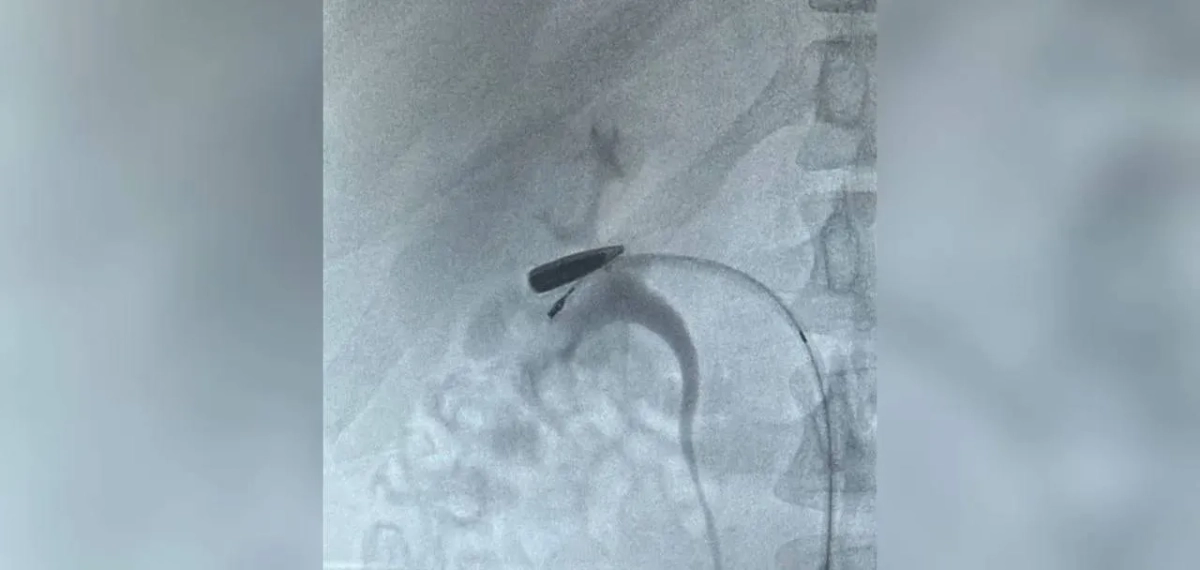

Из Курской области в Москву вертолётом эвакуировали мужчину с редким ранением: пуля калибра 5,45 мм, пройдя по венам от ключицы до области почки, остановилась в считанных миллиметрах от органа. Об этом сообщили в телеграм-канале Московская медицина.

Из Курской области в Москву доставили раненного с пулей в вене. Фото © Telegram / Московская медицина

«На КТ было обнаружено, что пуля мигрировала по верхней и нижней полым венам от места ранения и остановилась в правой почечной вене. Такой путь инородного тела — редчайший случай», — говорится в сообщении.

Хирурги института Склифосовского оперативно направили пациента в ангиографическую гибридную операцию, в ходе которой смогли извлечь пулю и восстановили кровоток. По словам медиков, мужчину удалось спасти, почка при этом не пострадала. Сейчас раненый находится в создании, его состояние оценивают как стабильное.